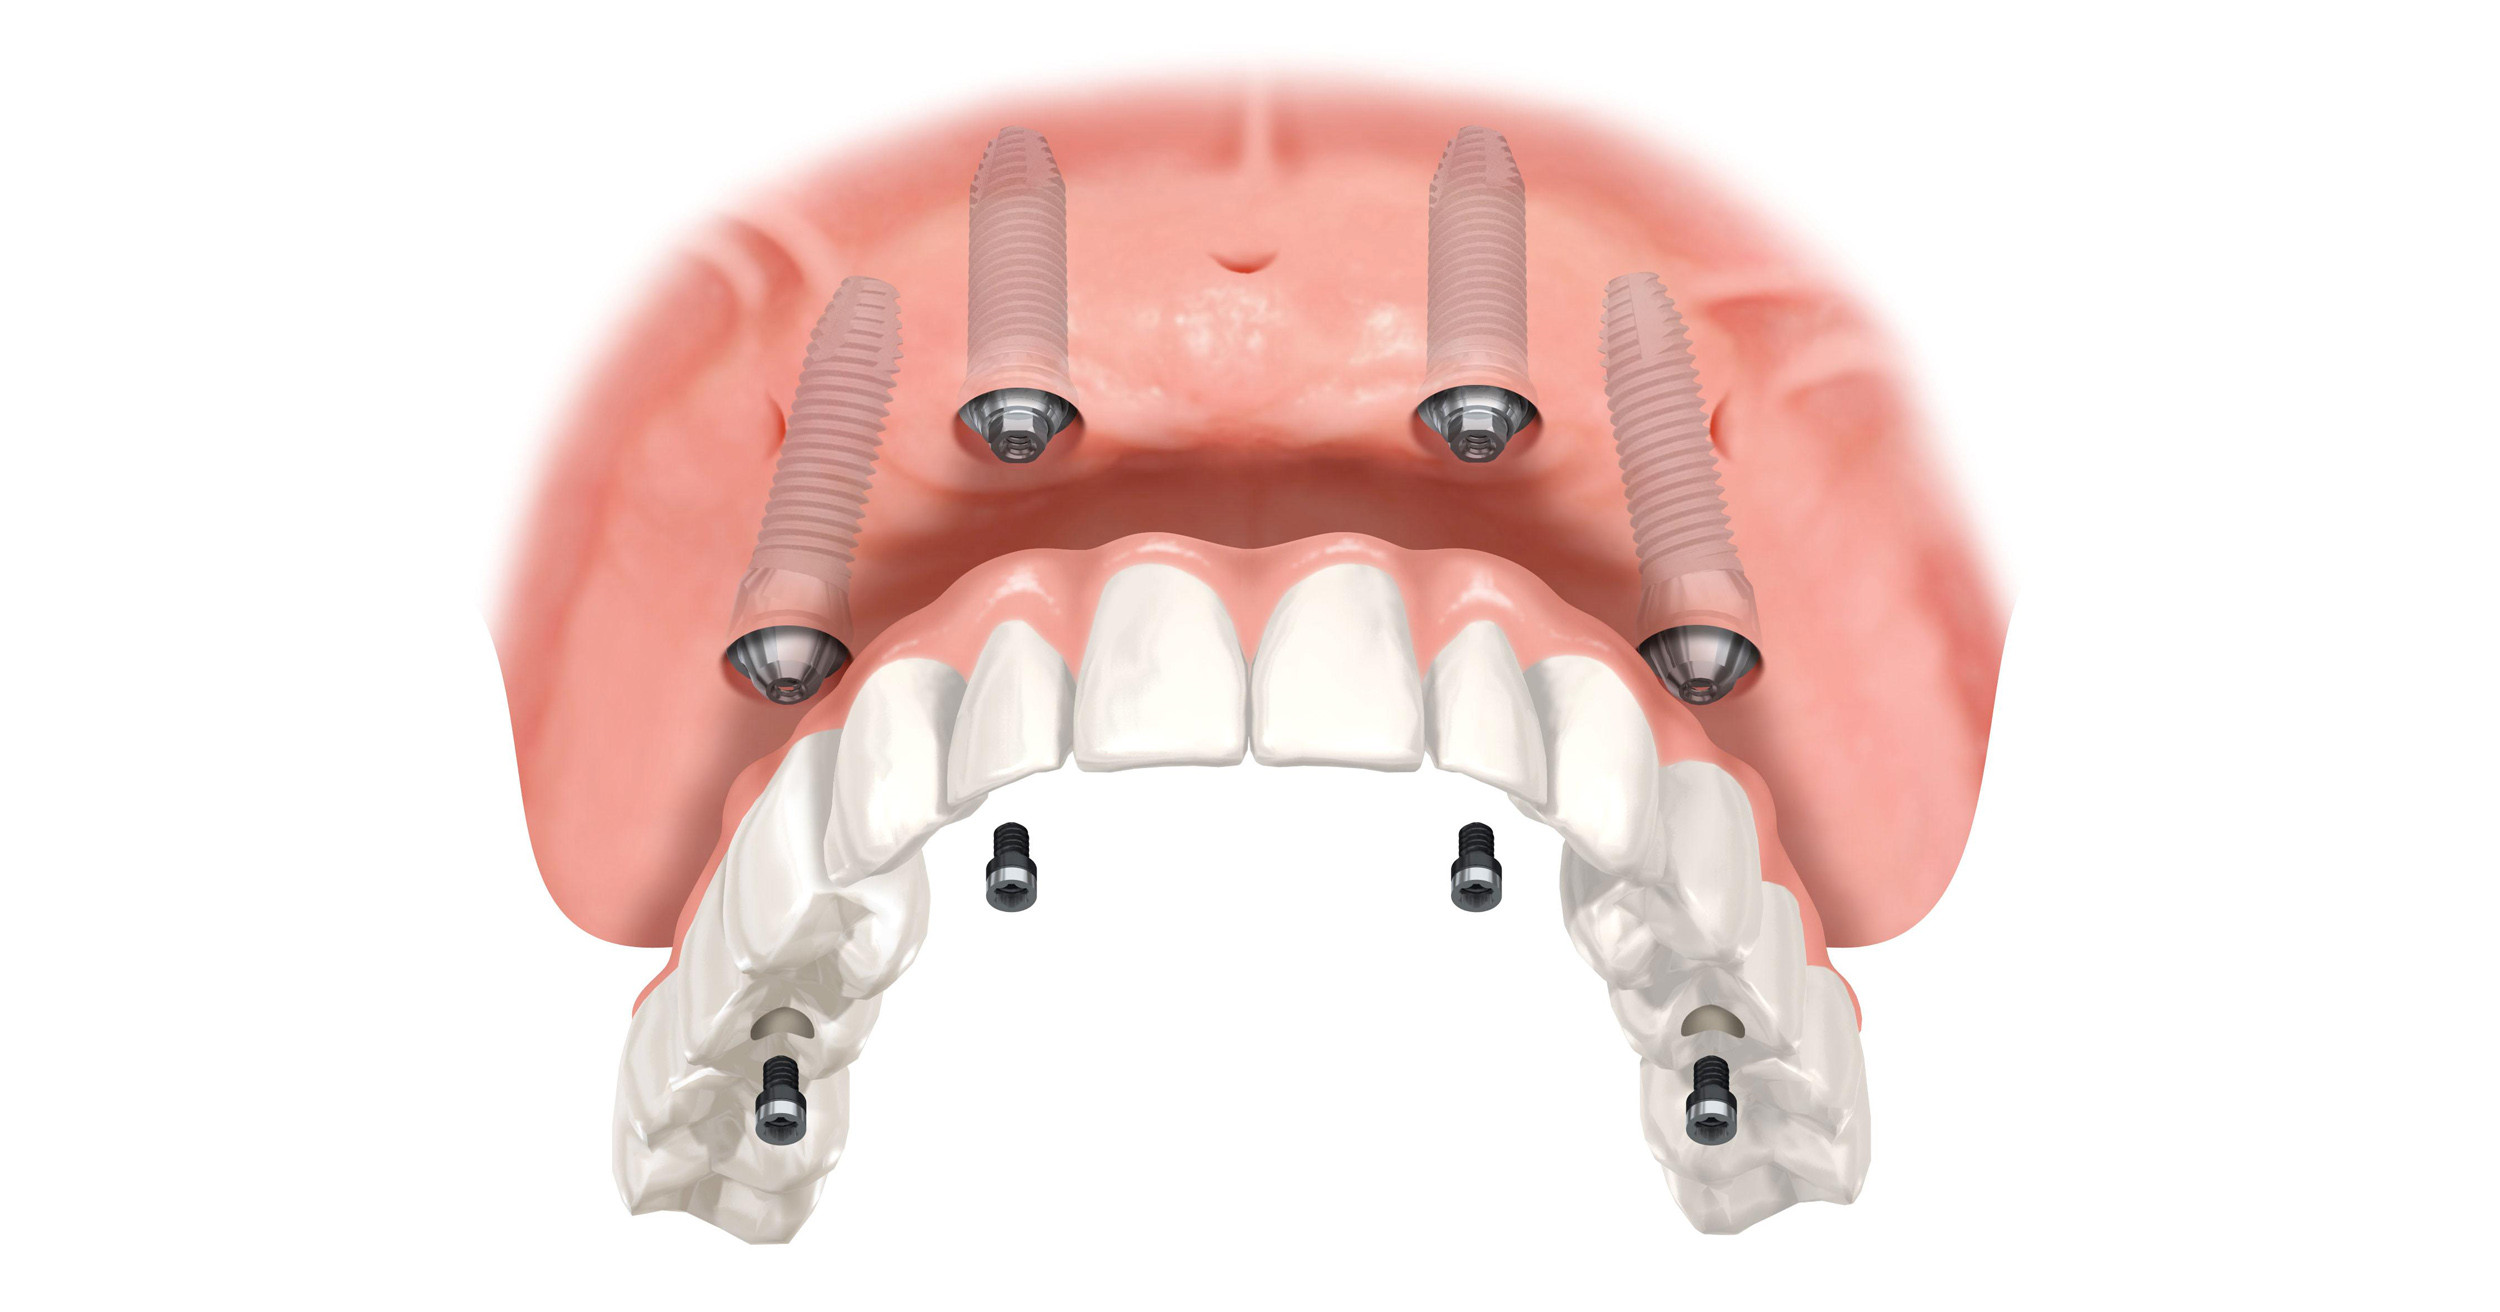

Пошаговое руководство по установке съёмного протеза на импланты